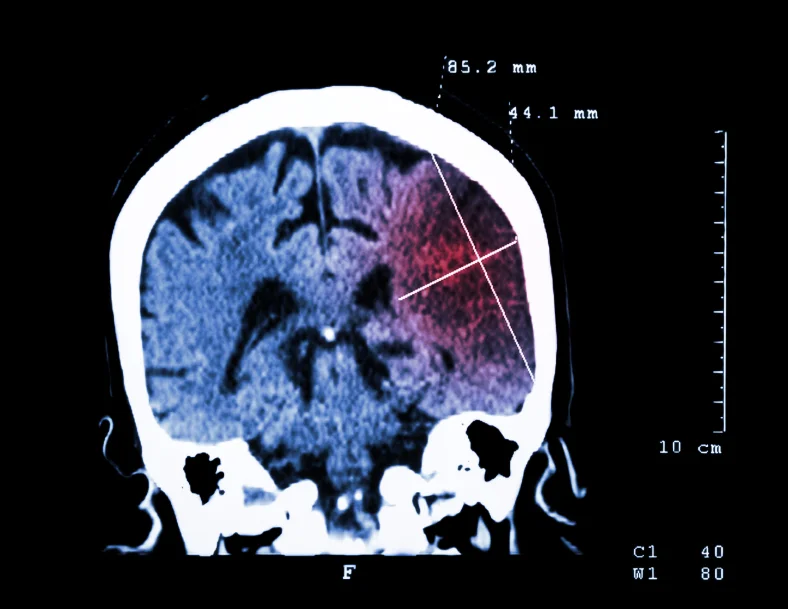

Read MoreSimilar to a heart attack, a stroke is actually a “brain attack.” A heart attack happens when blood suddenly is unable to reach a part of your heart but a stroke happens when blood supply cannot reach certain parts of your brain.

Read MoreOn average a person dies from a stroke every 4 minutes. Stroke is the third leading cause of death in the United States. Here are 7 of the most important signs of a stroke.